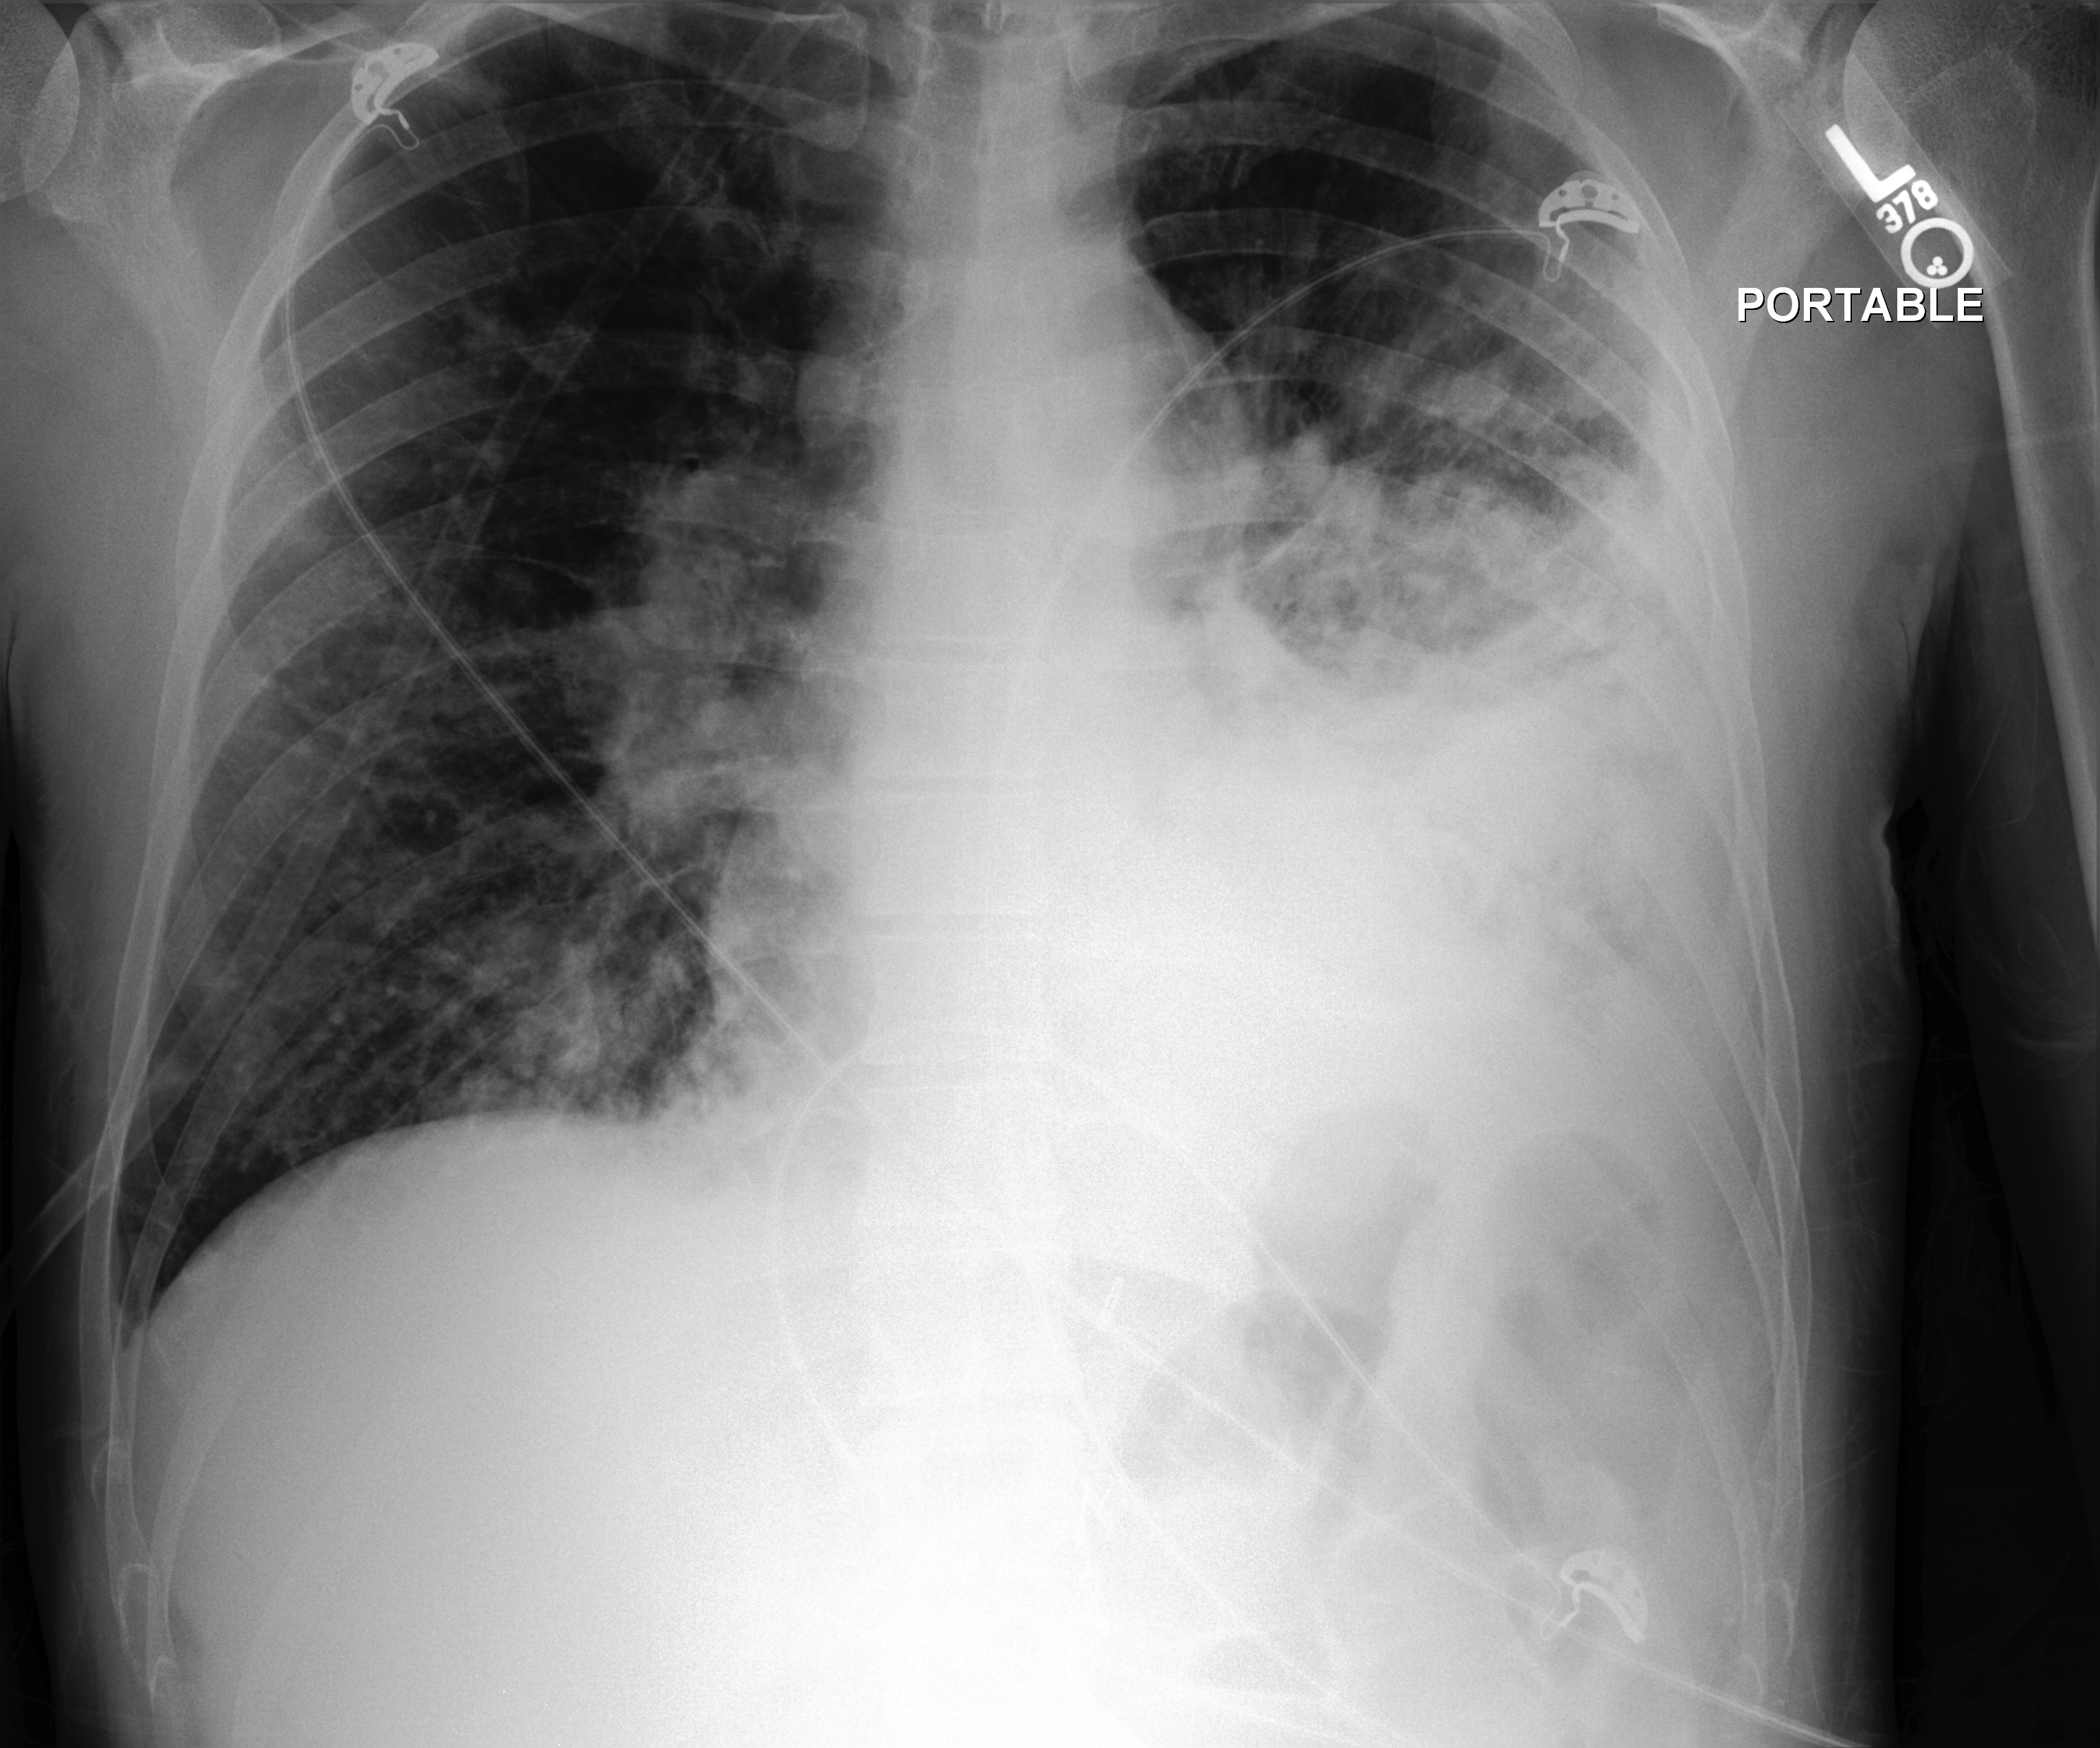

The results are shown in Table 2. Also, an example comparison of generated text from JRadiEvo and the ground truth on the test data is shown in Table 3.

| Example 1 | ||||||||

|

| Example 2 | ||||||||

| Example 3 | ||||||||